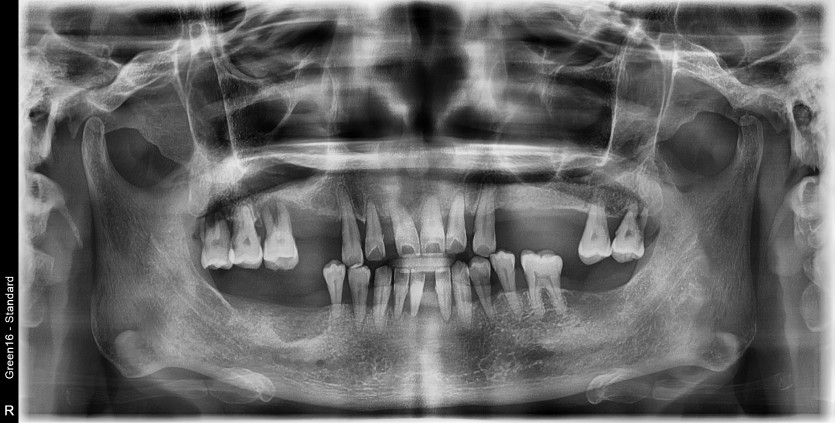

전체 임플란트 증례입니다.

18개의 임플란트로 완성하였습니다.